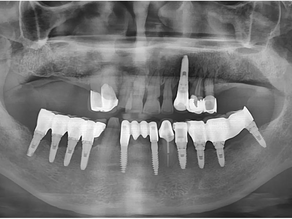

Full arch implant placement on the maxilla using Simplant software

Situation The patient was a 71 years old male with residual maxillary dentition using a partial denture of the upper arch. Pre-operative...